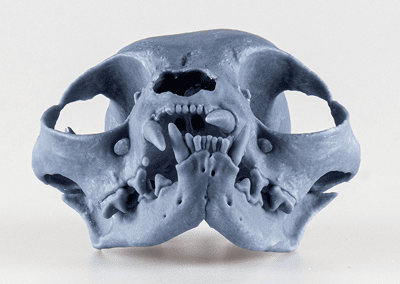

Train with a Realistic and Controlled Model

Traditional training methods leave too much to chance. GAIA Endobiomodels change that by offering a step-by-step, structured learning experience, designed to mimic real clinical cases with repeatability, progression, and total consistency.

Unlike extracted teeth, cadavers, or human dental models, GAIA provides a scalable, ethical, and 100% realistic way to train before working on real patients.

Structured difficulty progression for true mastery. ✔️ 9 clinical scenarios – 1-root, 2-root, and 3-root teeth. ✔️ 3 difficulty levels per case – Narrow, moderate, and wide canals. ✔️ 27 training combinations – From simple to complex, at your pace.

Every learner trains under identical conditions. Unlike extracted teeth or cadavers, GAIA provides a consistent model for all learners, ensuring fair skill development and predictable outcomes.